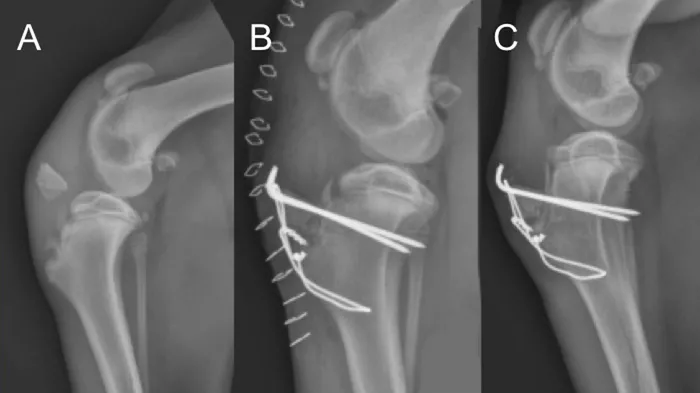

Physeal fractures can occur in any juvenile animal, even with little trauma, because the physis is weaker than the adjacent bone and ligaments. Orthogonal radiographs of any painful joint should be performed. Oblique projections, radiographs of the limb in different positions, and radiographs of the contralateral limb for comparison can all aid in the diagnosis of a physeal fracture. Shown here are lateral stifle radiographs from an 8-month-old mixed breed dog that presented for acute onset of lameness in the left pelvic limb after he slipped earlier that evening; pain was localized to the left stifle. Notice the open physes of the proximal tibia and distal femur, which are normal for a dog of this age. There is physeal separation and cranial displacement of the proximal epiphysis in the left tibia, and a greenstick fracture of the left fibula (arrows).